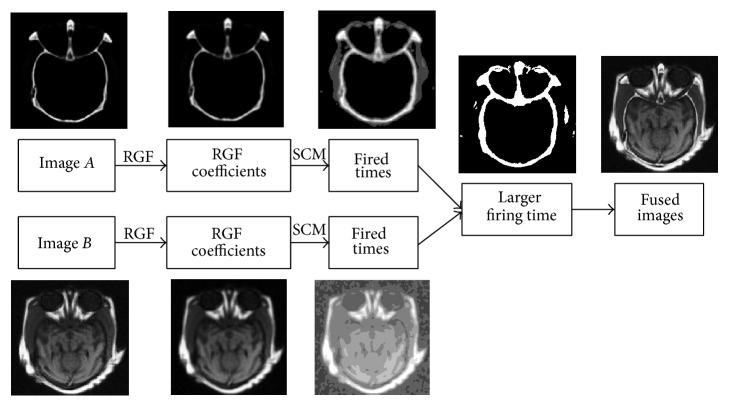

Medical image fusion plays an important role in diagnosis and treatment of diseases such as image-guided radiotherapy and surgery. Although numerous medical image fusion methods have been proposed, most of these approaches are sensitive to the noise and usually lead to fusion image distortion, and image information loss. Furthermore, they lack universality when dealing with different kinds of medical images. In this paper, we propose a new medical image fusion to overcome the aforementioned issues of the existing methods. It is achieved by combining with rolling guidance filter (RGF) and spiking cortical model (SCM). Firstly, saliency of medical images can be captured by RGF. Secondly, a self-adaptive threshold of SCM is gained by utilizing the mean and variance of the source images. Finally, fused image can be gotten by SCM motivated by RGF coefficients. Experimental results show that the proposed method is superior to other current popular ones in both subjectively visual performance and objective criteria.

医学图像融合在诸如图像引导放疗和手术等疾病的诊断和治疗中发挥着重要作用。尽管已经提出了许多医学图像融合方法,但这些方法大多对噪声敏感,通常会导致融合图像失真和图像信息丢失。此外,它们在处理不同类型的医学图像时缺乏通用性。在本文中,我们提出了一种新的医学图像融合方法来克服现有方法的上述问题。它是通过结合滚动引导滤波器(RGF)和脉冲皮层模型(SCM)实现的。首先,RGF可以捕捉医学图像的显著性。其次,利用源图像的均值和方差获得SCM的自适应阈值。最后,由RGF系数驱动的SCM可以得到融合图像。实验结果表明,该方法在主观视觉性能和客观标准方面均优于其他当前流行的方法。